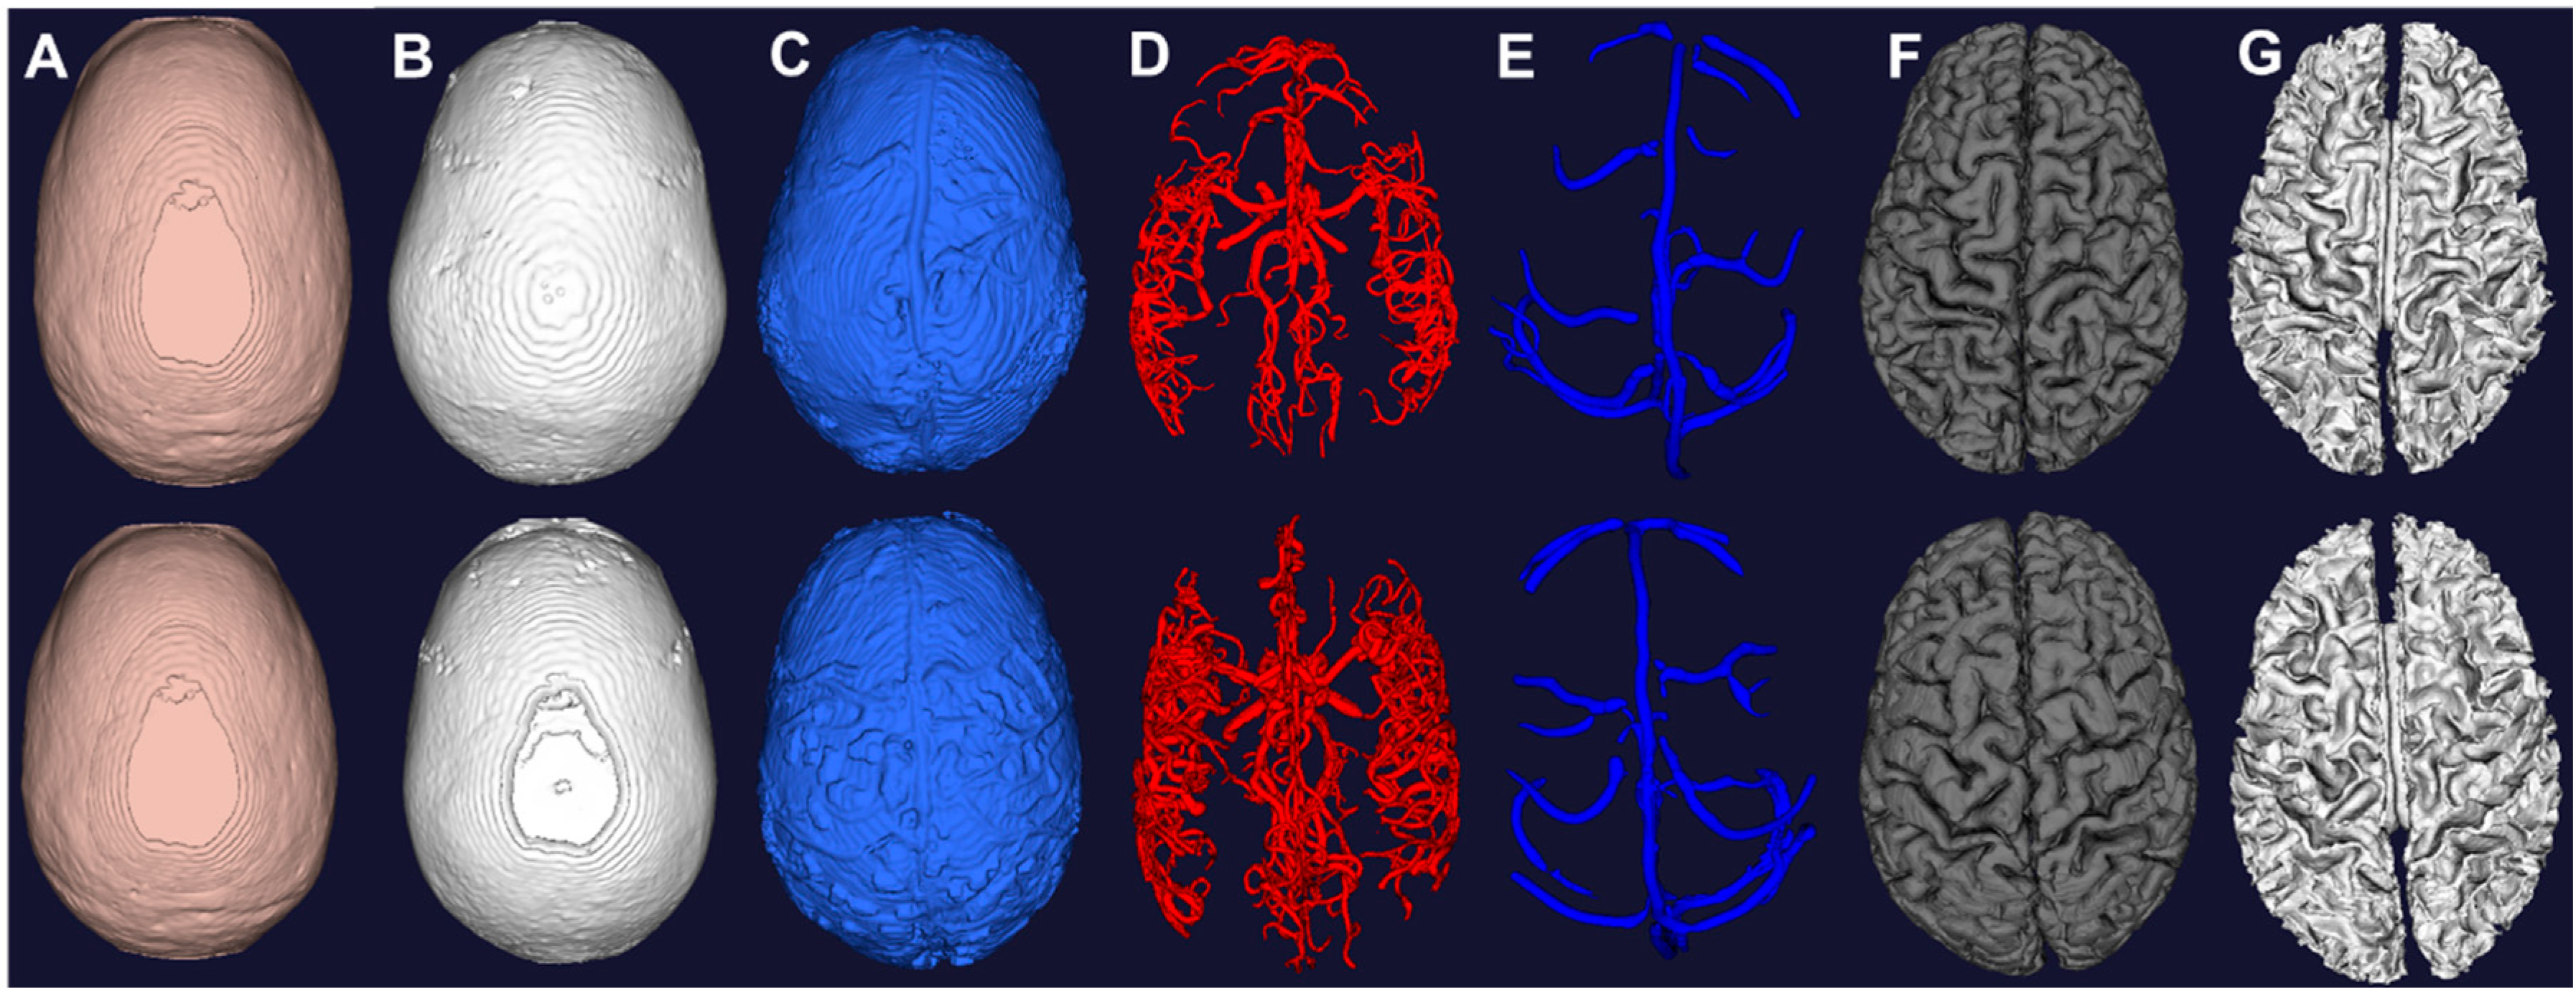

The T1 and T2 images in Figure 2 show clear delineation between the grey matter, white matter, and cerebrospinal fluid space. Figure 4 shows the segmented grey and white matter for the two subjects. The mesh vertices and faces are shown in Table 1. The meshes are generated with marching cubes along with binary images depicting the respective soft tissues. These images are used as input for skull and scalp segmentation.

Figure 4.

Computational meshes constructed from image segmentation of the two subjects. (A) Scalp from morphological operations of T1; (B) Skull from morphological operations of T1; (C) CSF from auto thresholding of T2; (D) Arteries from vessel filtering and segmentation of MRA; (E) Veins from vessel filtering and segmentation of MRV; (F) Grey matter from surface segmentation; (G) White matter from surface segmentation.

The brain mask is used to first determine the scalp mesh by removing the brain on the T1 image and thresholding. The skull is determined by removing the scalp and brain on the T1 image and another thresholding. The marching cubes algorithm is utilized to construct the meshes of skull and scalp of the two subjects as shown in Figure 4. The scalp exhibits high intensity outside at the exterior of the head in T1 and T2 images. The skull does not exhibit any signal and is hard to detect in all images. Thus, the morphological operation performed between the brain and scalp is used for approximating the skull. The skull is underestimated due to lack of signal by limitation of the imaging modality. CT can be used to achieve a better recognition of the skull with the tradeoff of exposure to ionizing radiation [46]. As pointed out by Dogdas et al. [34], the morphological operations and automatic thresholding might produce holes and it can be fixed by manually adjusting the threshold value. In our data sets, we did not find holes in our reconstructed meshes.

We compute four thresholds using Otsu’s method using the T2 image. The first threshold separates the background from other signals. The second threshold contains tissues with low intensity such as gray and white matter. All voxels above the second threshold are categorized as candidates for the cerebrospinal fluid space. The eyes also appears bright in T2 due to the aqueous humour in the eye. To exclude the eye, we look for the largest connected component and produced a binary image for mesh generation shown in Figure 4.

3.4. Vessel Segmentation

Figure 5 exhibits the MRA and MRV along with the filtered images. The MRA has high intensity in the large vessels, but the small vessels have similar intensity to the grey matter. After filtering, all vessels appear brighter which facilitates automatic vessel segmentation. The MRV imaging protocol was designed to remove non-vascular tissues inherently but the small veins are still difficult to detect. After filtering, all veins have high intensity and the filtered image is used for segmentation. The MRA imaging protocol was designed to enhance intensity for high flow areas which also includes signals from the superior sagittal sinus. The contamination from the vein was removed by excluding common voxels between MRA and MRV. After applying our vessel filter, it is shown that the non-vascular tissues were suppressed and small vessels are enhanced. The filter images then served as input for the centerline and diameter extraction. The vessel mesh was reconstructed using the diameter and centerline information shown in Figure 4.

3.5. Whole Brain Mesh Generation

Figure 4 displays the individual meshes reconstructed from the proposed pipeline for the two subjects. Mesh metrics are evaluated in Table 1 and compared with physiological values [47,48,49,50,51,52]. The grey matter volume for both subject falls within the reported range of 710–980 mL. The white matter volume also for both subjects are also within reported values of 260–600 mL. The arterial and venous volume are slightly lower than reported values due to limited image resolution. The CSF volumes for both subjects in the lateral ventricles, third ventricles are fourth ventricles are all comparable to reported values. The scalp surface area for both subjects are approximately 10% higher than the reported value of 600 cm2. It demonstrates the ability of our pipeline to process image signals to reconstruct meshes for display and simulation. However, due to limited resolution and partial volume effect, the meshes intersect with each other at the boundaries which is not anatomically accurate. This inaccuracy appears mostly at the deep gyri, in which the small vessels are embedded with the cerebrospinal fluid. To compensate for the hardware limitations, we used the binary images to detect for intersections and excluded common voxels. One can also pursue Pons’s method to produce watertight meshes [25].